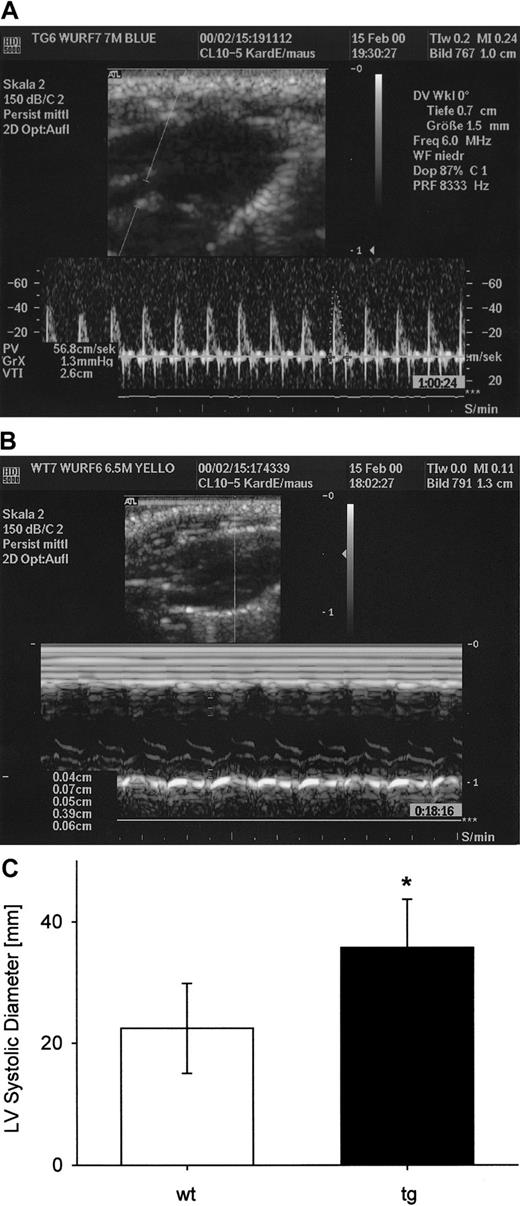

Invasively measured mean arterial pressure (Figure5A) did not differ between wt and tg mice. HR (wt: 529 ± 49 beats per minute; tg: 497 ± 56 beats per minute) as well as arterial pO2 (wt: 158 ± 23 mm Hg; tg: 146 ± 74 mm Hg) in mice spontaneously breathing room air supplemented with O2 were also similar. Central venous pressure was significantly (P < .05) higher in tg compared with wt mice, indicating an increased cardiac preload in the tg animals (Figure 5B). Pulsed Doppler measurements by noninvasive high-frequency echocardiography revealed that there was no significant difference of cardiac output between wt and tg mice (Figures 5C,6A). In the echocardiographic M-mode investigation (Figure 6B,C), left ventricular systolic diameter and left ventricular end-diastolic diameter (data not shown) were significantly increased in tg animals. Fractional shortening of the left ventricle in tg mice was reduced by 25%.

Representative transthoracic high-frequency echocardiograms.

(A) Pulsed Doppler tracing of the left ventricular outflow tract measured just above the aortic valve without angle correction. (B) M-mode echocardiogram in the parasternal long-axis view. (C) Systolic diameter of the left ventricle (M-mode long-axis view, wt: 11 measurements in 6 mice; tg: 10 measurements in 5 mice) was significantly increased in tg mice, *P < .05.